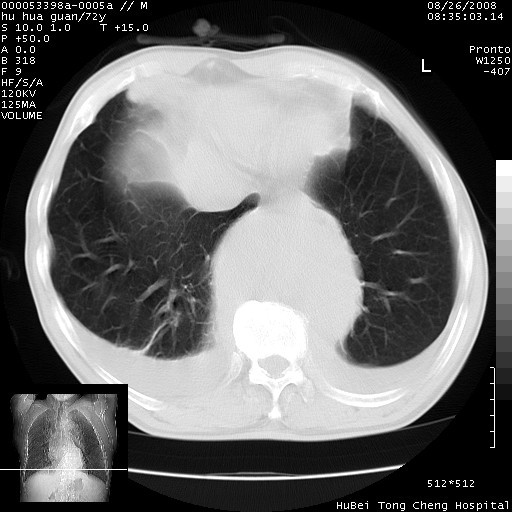

可以明确的说。肯定不是主动脉夹层破裂出血!考虑为淋巴瘤或间叶组织来源的恶性肿瘤可能性大。右肺小结节建议薄层观察,如能发现恶性征象,那椎前改变就考虑为转移所致。至于双侧少量胸水乃静脉血回流受阻所致。

1、右肺周围性肺癌、胸腔积液(双)

2、建议食道吞钡和增强检查排除食道和主动脉病变

3、后纵隔淋巴类肿瘤

降主动脉前移位,后纵隔占位

后纵隔占位,降主动脉前移位;双侧胸腔积液;应排外食管病变侵犯血管可能;